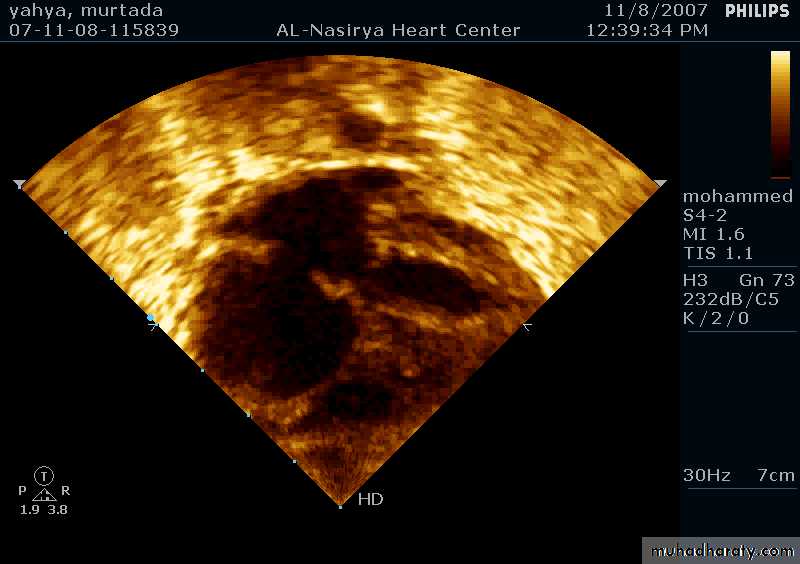

33Echocardiography & TEE

Shows the size of the defectThe direction of blood flow

The pulmonary artery pressure34

Ostium Secundum ASD

36